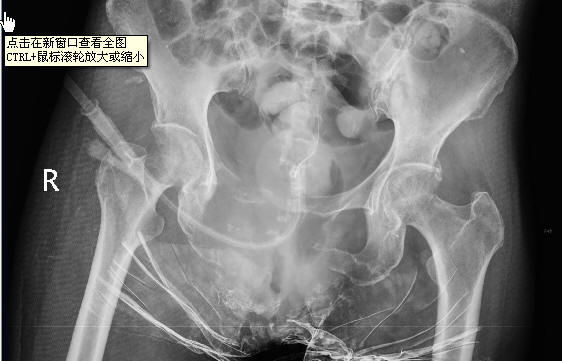

女性,会阴癌术后,现局部右软组织肿块并破溃。

耻骨联合及双侧耻骨、坐骨溶骨性骨质破坏,支持转移瘤。

双侧耻骨 坐骨及右股骨头部均见溶骨性破坏,支持转移瘤

双侧坐骨\\耻骨及耻骨联合破坏吸收,伴软组织影'结合病史支持转移.